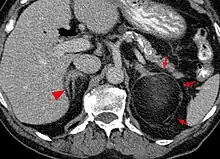

Diagnosis

Most myelolipomas are unexpected findings on CT scans and MRI scans of the abdomen. They may sometimes be seen on a plain X-ray films.[4]